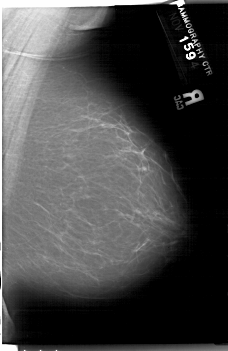

A_1202_1.RIGHT_MLO

RIGHT_MLO LINES 6661 PIXELS_PER_LINE 4321 BITS_PER_PIXEL 12 RESOLUTION 43.5 NON_OVERLAY

FILE: A_1202_1.LEFT_CC.OVERLAY

TOTAL_ABNORMALITIES 1

ABNORMALITY 1

LESION_TYPE CALCIFICATION TYPE PLEOMORPHIC DISTRIBUTION SEGMENTAL

ASSESSMENT 5

SUBTLETY 3

PATHOLOGY MALIGNANT

TOTAL_OUTLINES 1

BOUNDARY